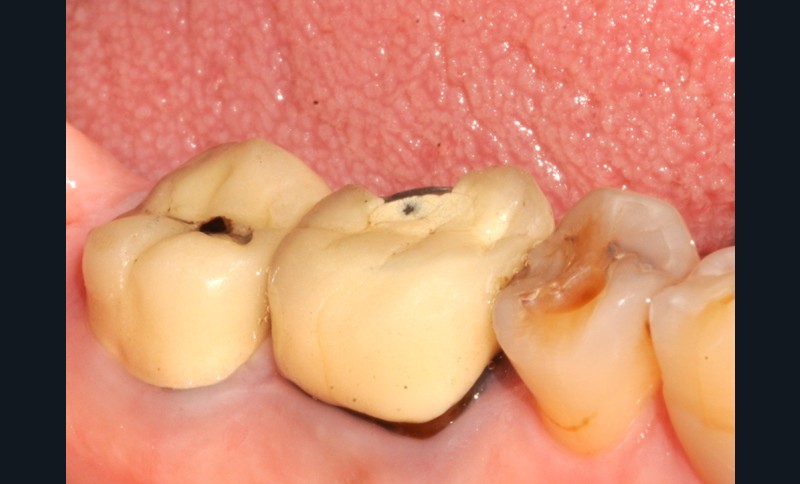

Aspect clinique et radiographique des lésions d’abrasion

Cliniquement, les lésions d’abrasion sont caractérisées par des facettes lisses, une absence de convexité et des bords à angles vifs. La flexibilité du ligament alvéolo-dentaire va entrainer un frottement au niveau des points de contact, qui peuvent se transformer en surfaces de contact (fig. 2c-d, 3 et 4b-c).

Radiographiquement, on observe une perte des cuspides et un aspect plan des faces occlusales (fig. 2a-b et 4a).